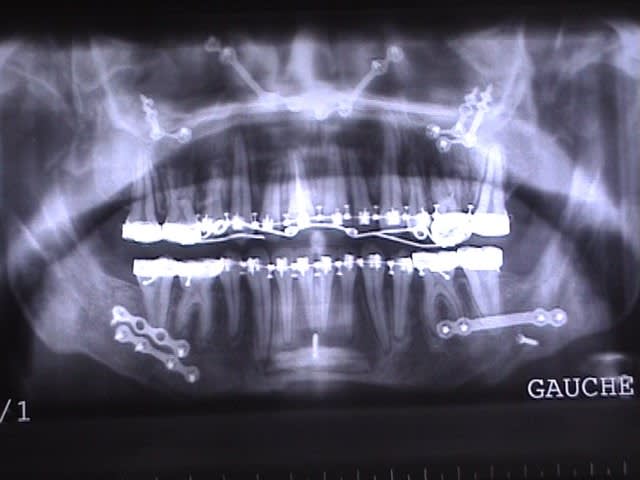

Cas extrême ? J’ai mieux que cela (fig. jointes).

Ami d’Eugénol qui lis ces lignes, rassure-toi ! Ce sont des cas de chirurgie maxillo-faciale qui n’ont rien à voir avec les cas d’ancrages osseux orthodontiques, ni avec la discussion en cours. Notre bon Bjc a introduit cet aparté car il aime bien les facéties.